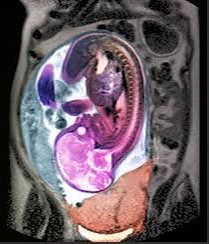

怀孕期间的肥胖会增加一些健康问题,包括与高血压和糖尿病有关的问题。妊娠期高血压或先兆子痫可导致严重并发症,导致癫痫发作、心肌梗塞和中风,以及影响胎儿生长的胎盘问题。

肥胖还会增加患妊娠糖尿病的风险,一般在妊娠 26 至 28 周左右进行筛查。妊娠糖尿病对母亲和胎儿都有严重影响,包括增加肩难产、巨大儿和剖宫产的可能性。它还增加了母亲及其孩子患糖尿病的终生发病率。

肥胖会带来延伸至胎儿的独特风险,例如神经管缺陷、心脏异常和口面裂。不幸的是,产前胎儿解剖调查的质量和产前诊断筛查计划的某些方面受到很大限制。对于 BMI 大于 35 kg/m2 的人,建议进行 2 级详细形态扫描,对于 BMI 大于 40 kg/m2 的人,建议进行胎儿超声心动图检查。

怀孕期间的肥胖既增加了出生缺陷的风险,又降低了识别的敏感性。成像和心率监测带来了更多挑战。增加的成像要求、患者的不满和增加的评估成本也可能是巨大的。对于最常见的胎儿非整倍体(例如 21 三体),较新流行的无创产前检测在第一次抽血时,由于胎儿分数低于指定的临界值,与正常体重类别相比,其不确定结果的发生率也更高。

胎盘功能的变化在妊娠并发症的发展中起着关键作用,但也可能与母体肥胖与婴儿的长期健康风险有关。新生儿期高胰岛素血症和低血糖症的发展增加是常见的。